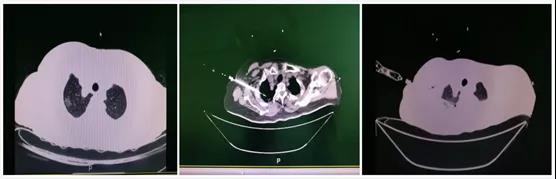

手术在CT室进行,首先对患者肺结节在CT下做了精确定位,然后使用直径仅为3mm的电极针穿刺至结节位置,给电极针提供电流,使其产生高频电磁场致局部产热,从而使结节细胞发生凝固性坏死。整个手术在局麻下完成,射频过程患约15分钟,无切口、患者无明显不良反应,无手术痛苦,术后几小时患者即可自由活动,无不适症状发生。